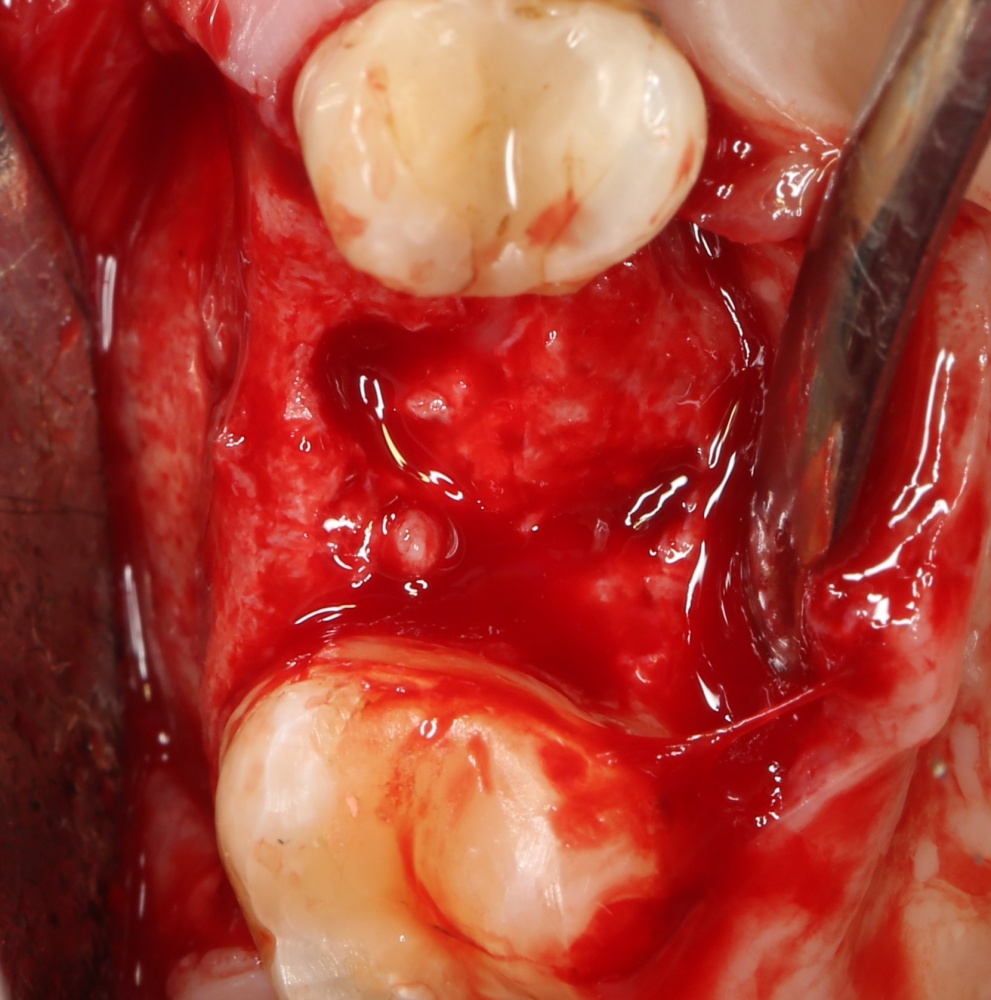

Как на фотографии выше — из-за целого ряда вмешательств и существовавшего ранее ороантрального соустья можно сказать, что от слизистой оболочки верхнечелюстной пазухи почти ничего не осталось. Можем ли мы как-то закончить эту работу? Легко:

Первая операция — мы не можем сразу поставить имплантат из-за почти полного отсутствия кости между полостью рта и дном верхнечелюстной пазухи: